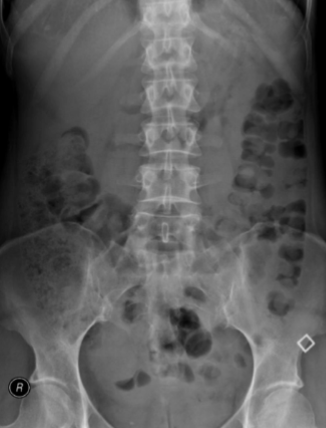

What is this and what type of scan

AAA, Abx